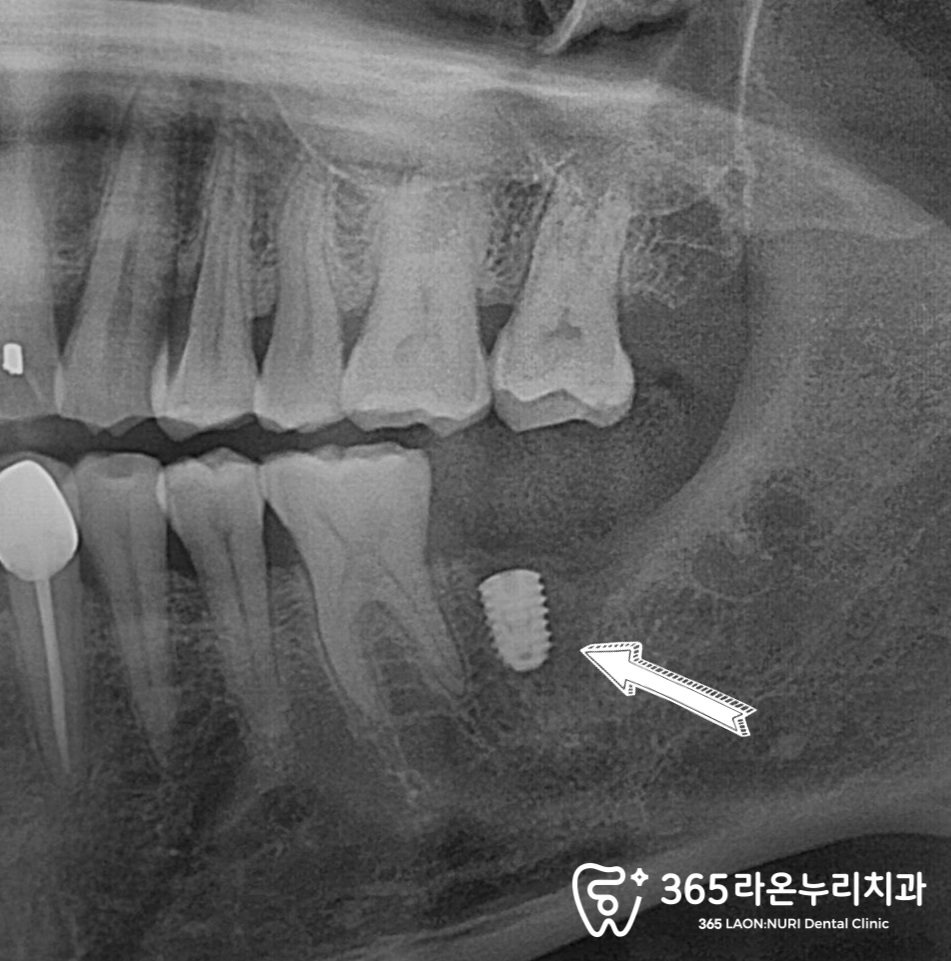

식립 후 촬영한 파노라마를 오산역 치과 에서

보면 미리 모의 식립을 진행한 덕분에

별 다른 문제 없이 안정적으로

식립에 성공한 모습을 볼 수 있었습니다.

여기서 바로 크라운 수복을 진행하지 않고

픽스처와 골이 온전히 유착될 수 있도록

기다리는 시간을 가지게 되는데요.